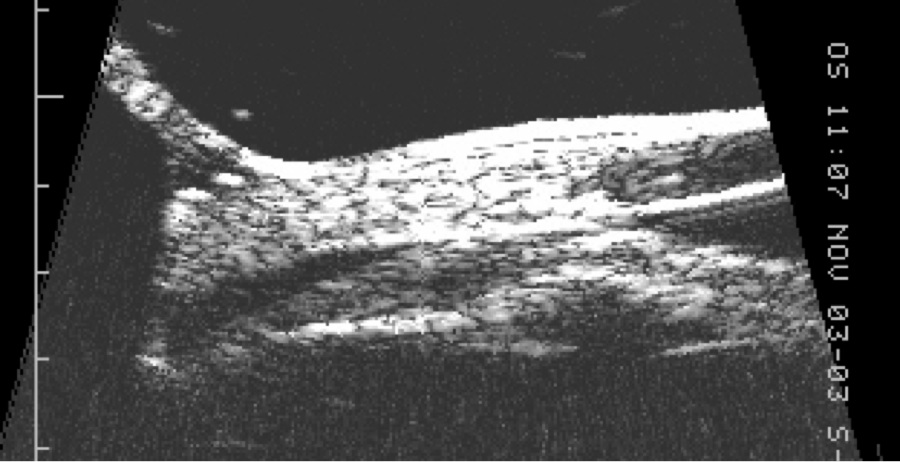

Figure 2. UBM demonstrating cyclodialysis cleft in patient (a) above

UBM makes use of a high frequency B-scan transducer (50-100 MHz) to image anterior segment structures with very high (25 to 50 micron) resolution (Figure 2). It produces extremely detailed images of the anterior chamber, angle and ciliary body, and is thus the best device for determining the presence and size of cyclodialysis clefts and any associated anterior suprachoroidal fluid. In a series of six eyes with post-traumatic hypotony and suspected cyclodialysis, gonioscopy revealed a cleft in only one while UBM identified clefts in all six.[10] UBM also facilitates detection of clefts in the presence of a cloudy cornea where gonioscopy is not helpful. However, UBM technology is somewhat inconvenient for the patient; older models required immersion of the globe in a water bath with the patient supine, while newer models incorporate the water bath into the probe but still require direct ocular contact with coupling gel.